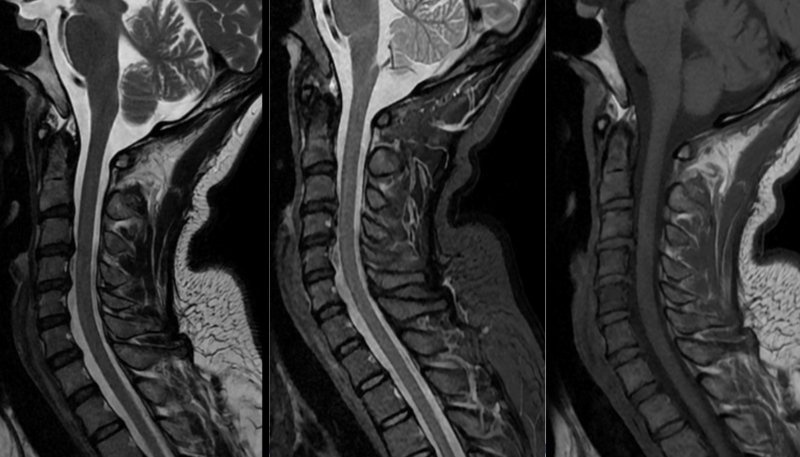

| Hình ảnh chụp MRI cột sống cổ của bệnh nhân. |

Khi tình trạng trở nên nghiêm trọng, chị đến khám tại cơ sở y tế và được chỉ định chụp cộng hưởng từ (MRI) sọ não và cột sống cổ. Kết quả cho thấy chị bị thoát vị đĩa đệm tại nhiều tầng cột sống cổ như C3/C4, C4/C5, phình đĩa đệm C6/C7 kèm theo thoái hóa đốt sống. Hình ảnh não ghi nhận một số biến đổi nhẹ ở chất trắng. Từ đó, bác sỹ chẩn đoán chị mắc đau dây thần kinh chẩm trên nền thoái hóa và thoát vị đĩa đệm cột sống cổ.